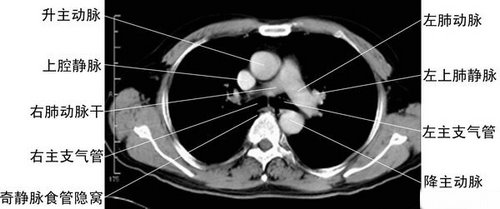

气管分叉层-胸部CT断层影像

气管分叉层面-胸部CT断层影像